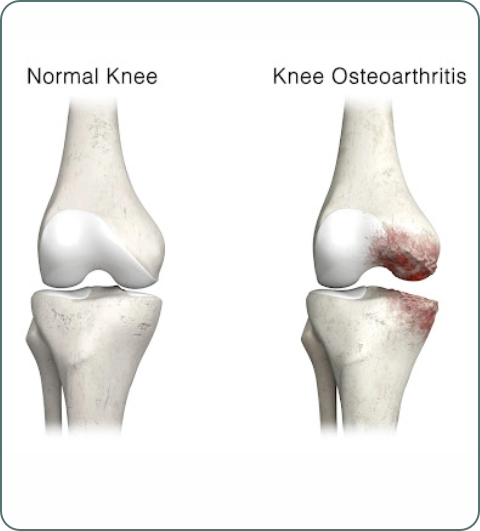

Osteoarthritis

Degenerative joint disease causing cartilage breakdown. Common in knees, hips, and spine. Symptoms: joint pain, stiffness, swelling, reduced mobility, especially after activity.